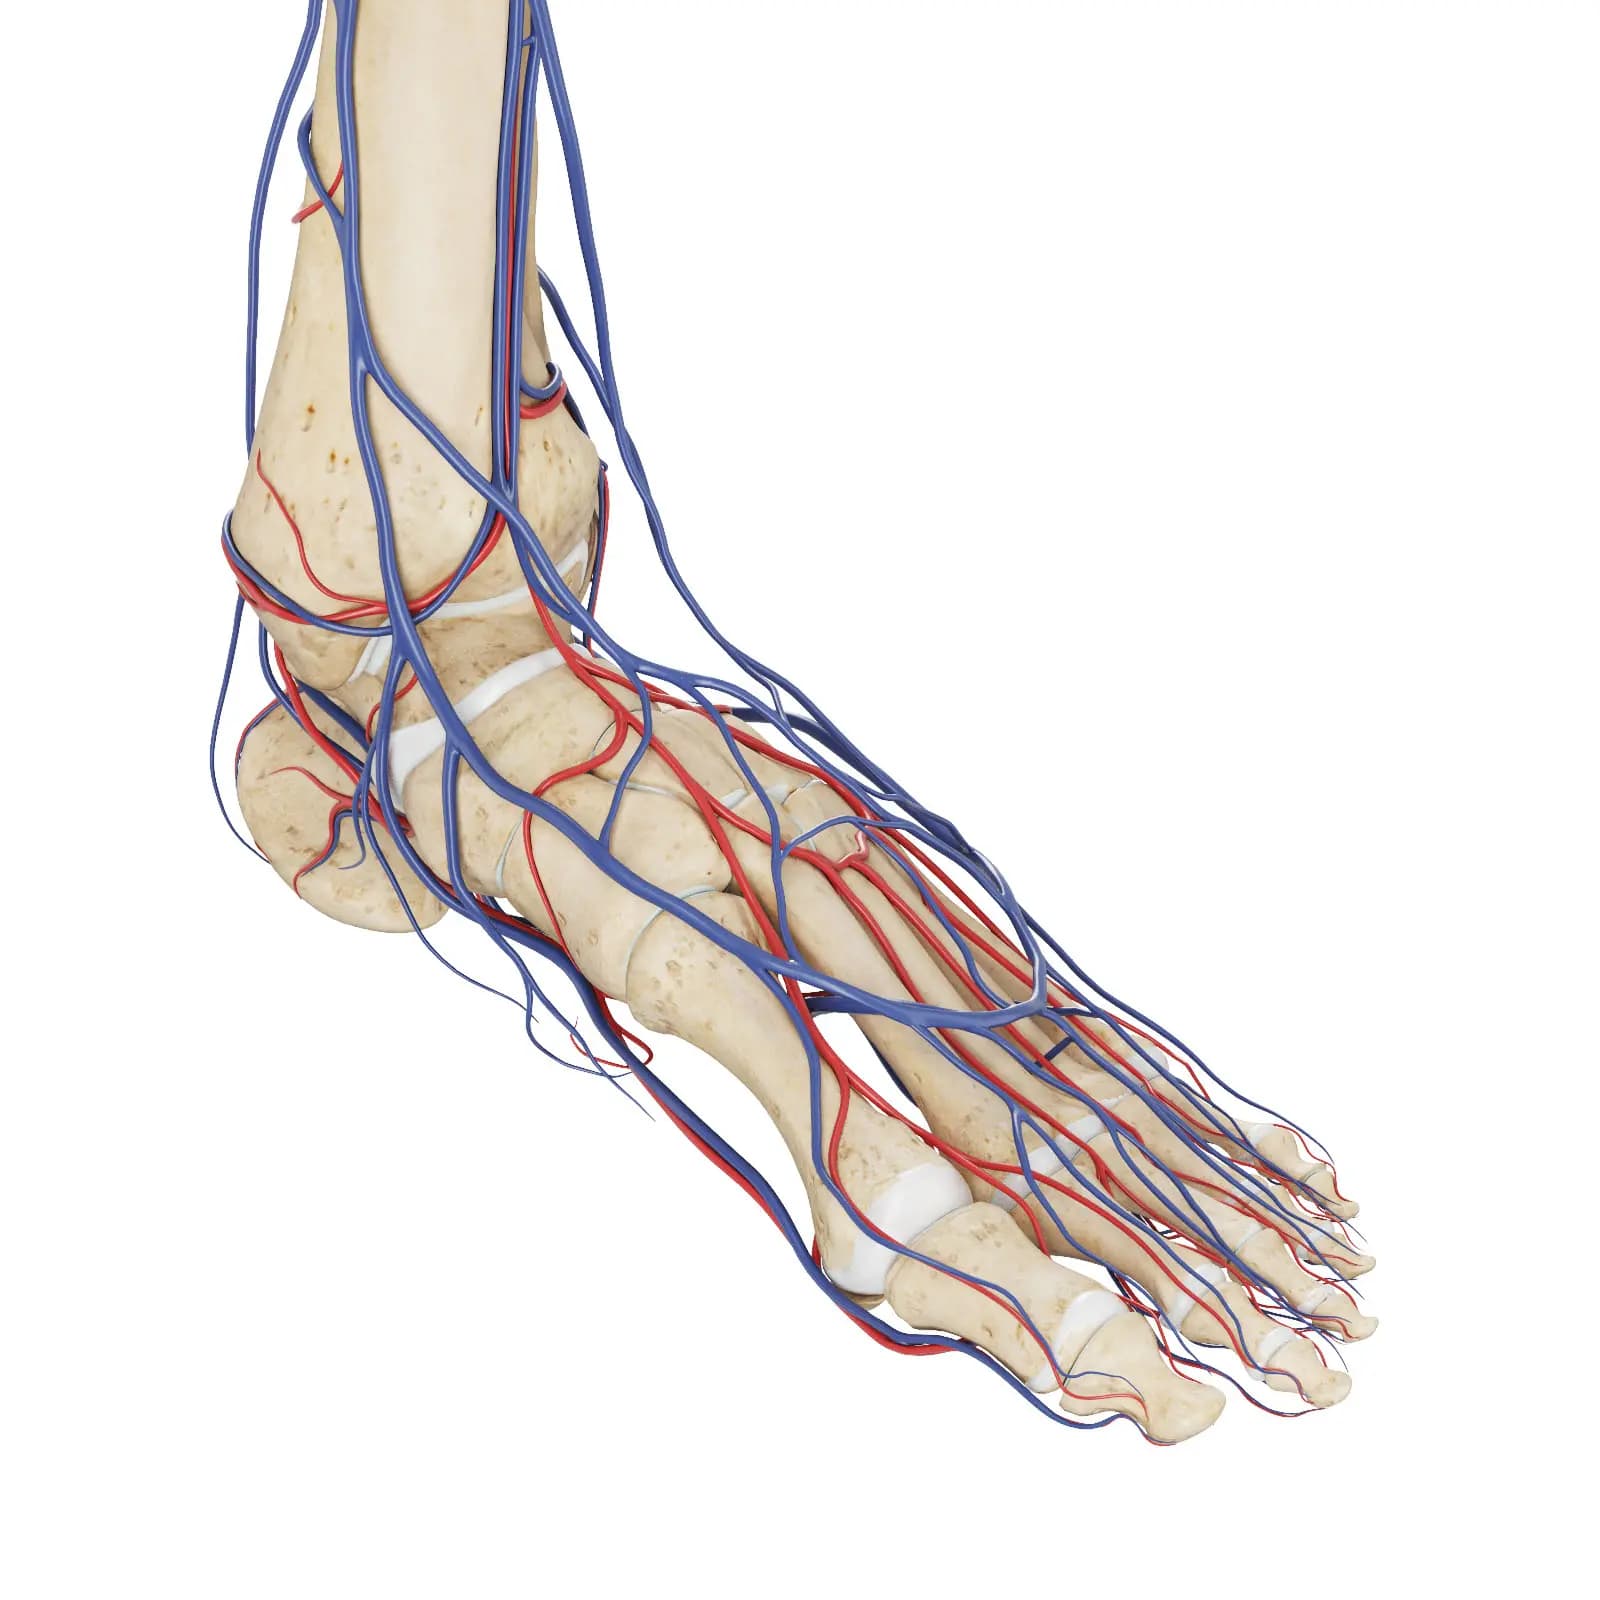

3d Rendered Medical Illustration Of The Vascular System Of The Foot